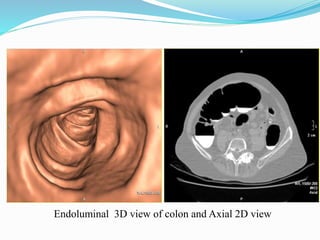

This document discusses colorectal polyps. It defines polyps and describes their types, including neoplastic and non-neoplastic polyps. It discusses adenomatous polyps in depth, noting their malignant potential increases with size over 1cm and villous architecture. Radiological diagnostic methods for polyps including single and double contrast barium enema and CT colonography are explained. The document provides an overview of polyp pathogenesis and genetic syndromes like FAP that increase cancer risk.